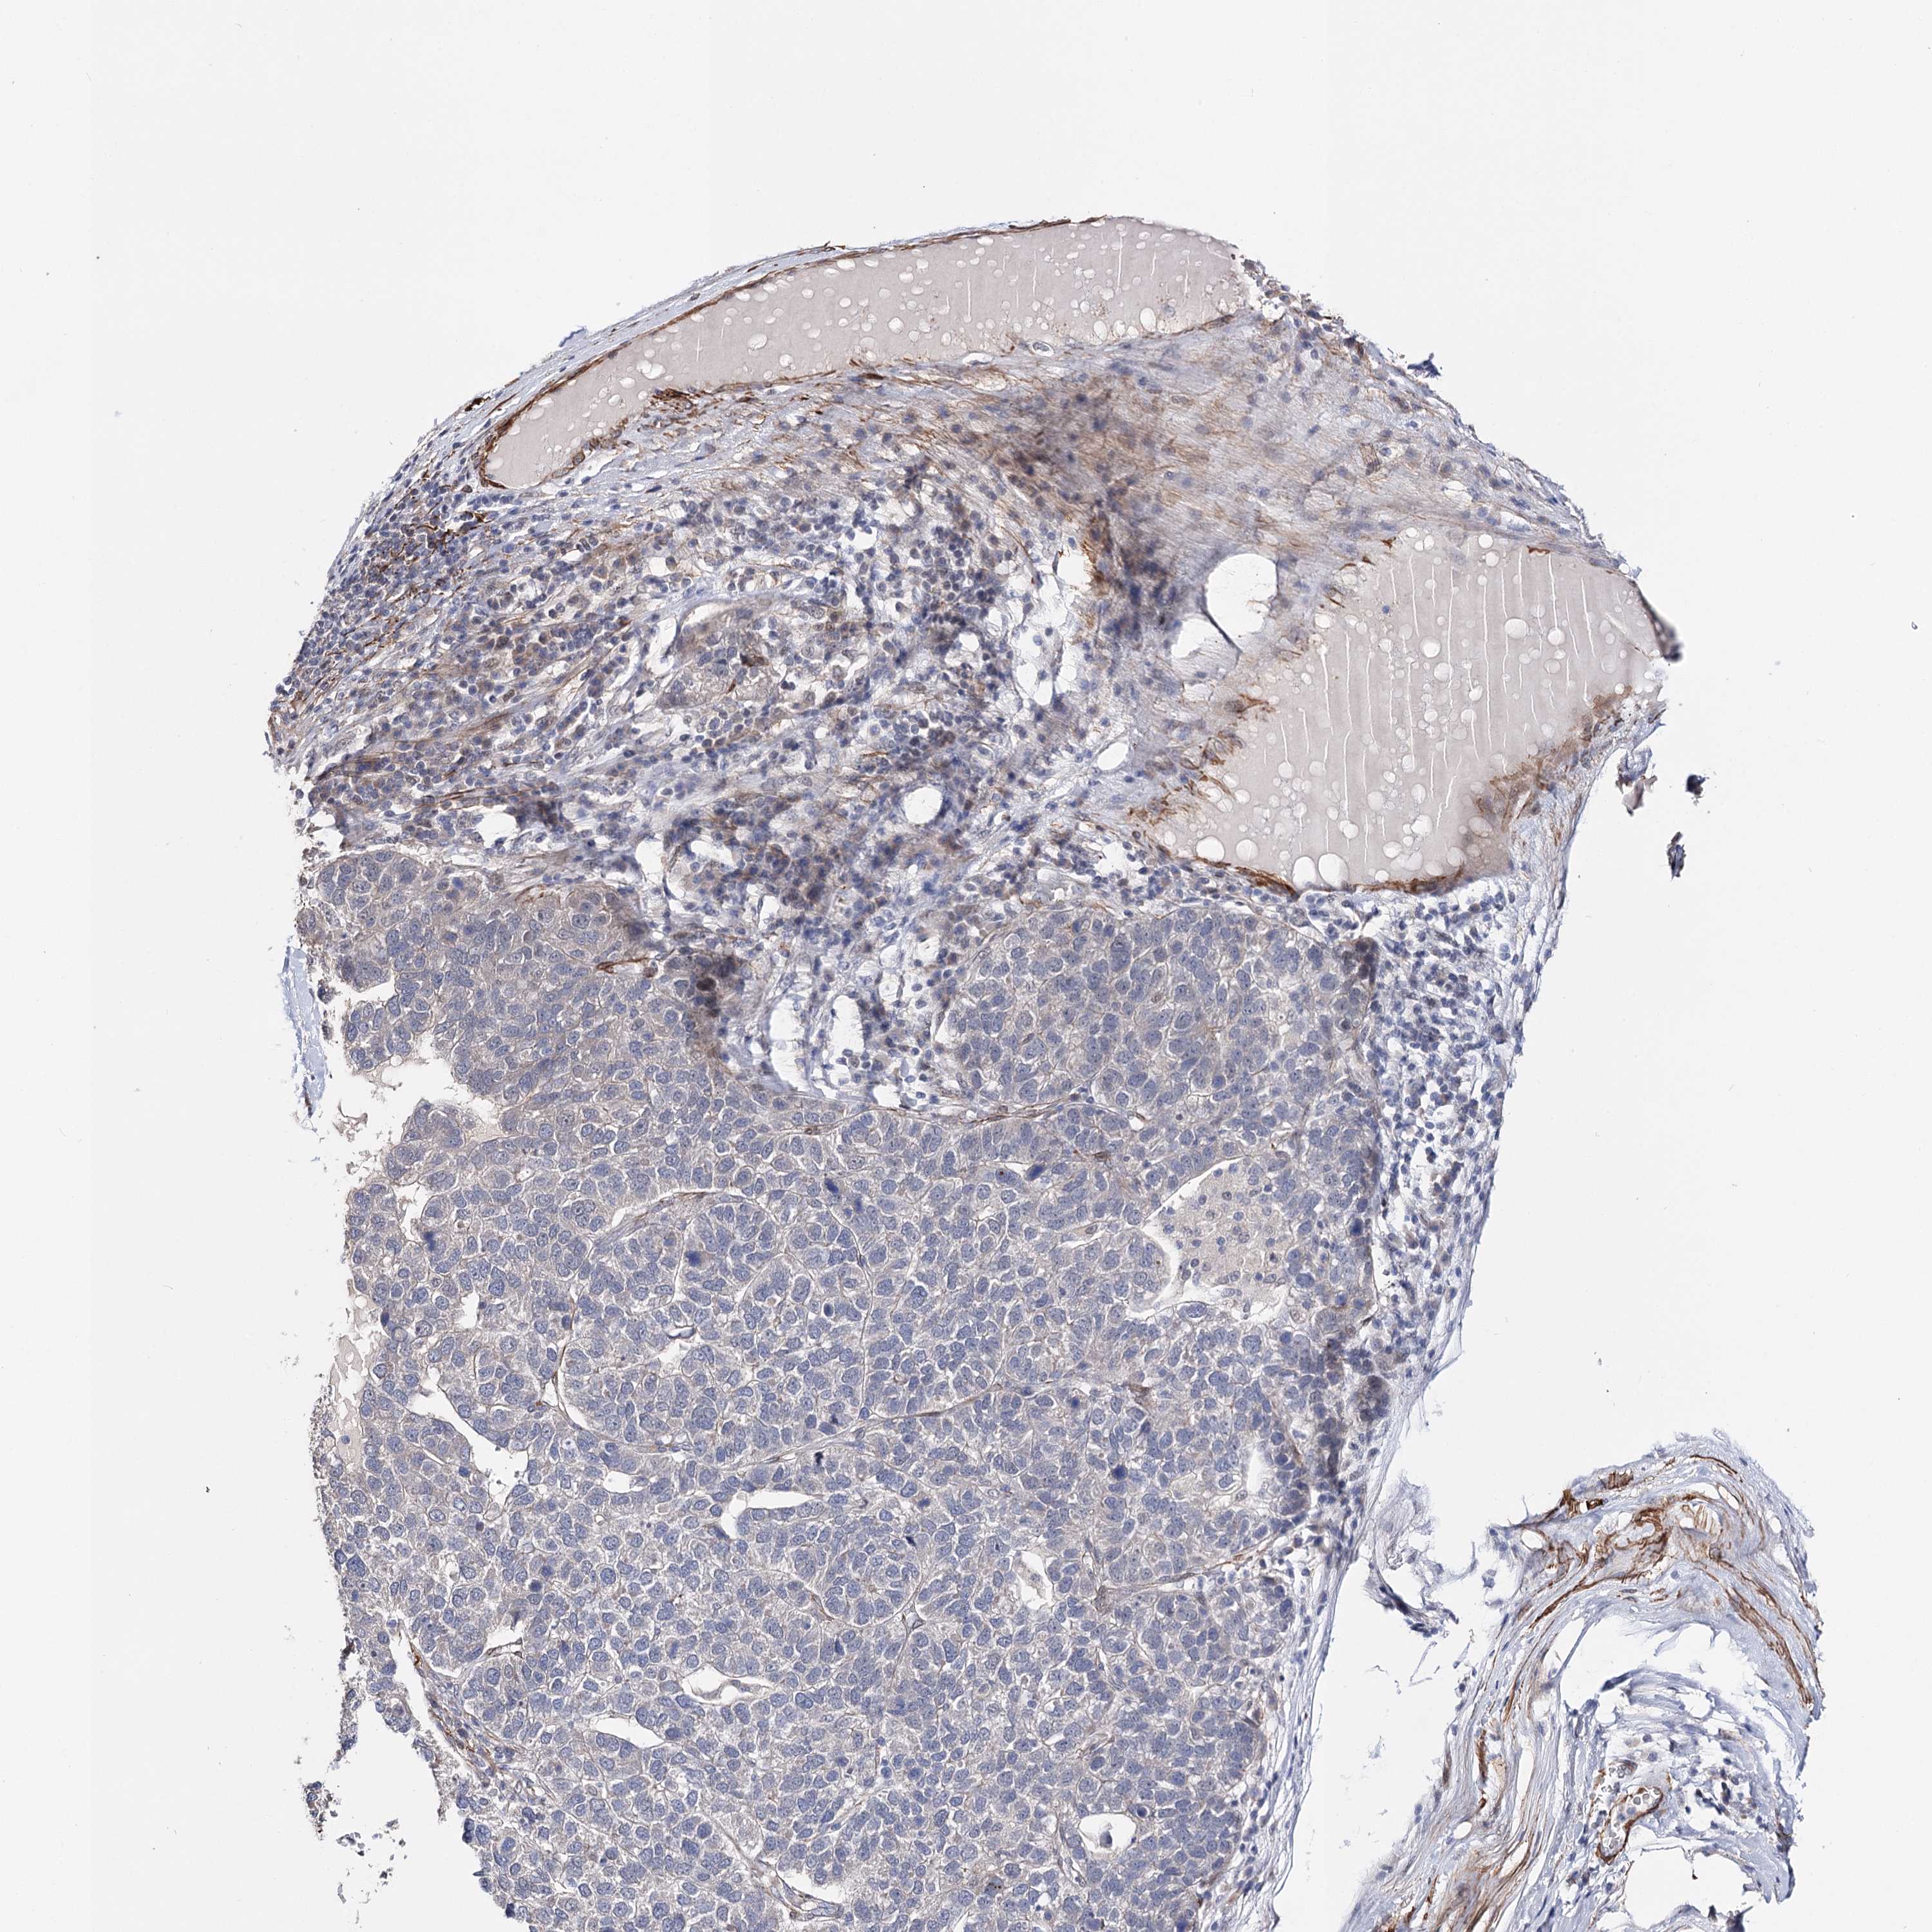

PANCREATIC CANCER - Protein expressioni

A mouse-over function shows sample information and annotation data. Click on an image to view it in a full screen mode. Samples can be filtered based on level of antibody staining by selecting one or several of the following categories: high, medium, low and not detected. The assay and annotation is described here.

Note that samples used for immunohistochemistry by the Human Protein Atlas do not correspond to samples in the TCGA dataset.

Antibody stainingi

Antibody staining in the annotated cell types in the current human tissue is reported as not detected, low, medium, or high, based on conventional immunohistochemistry profiling in selected tissues. This score is based on the combination of the staining intensity and fraction of stained cells.

Each image is clickable and will lead to virtual microscopy that enables deeper exploration of all samples and also displays staining intensity scores, fraction scores and subcellular localization as well as patient and tissue information for each sample.

Antibody HPA037786

Antibody HPA038034

Antibody HPA038867

Antibody HPA038868

Adenocarcinoma, NOS